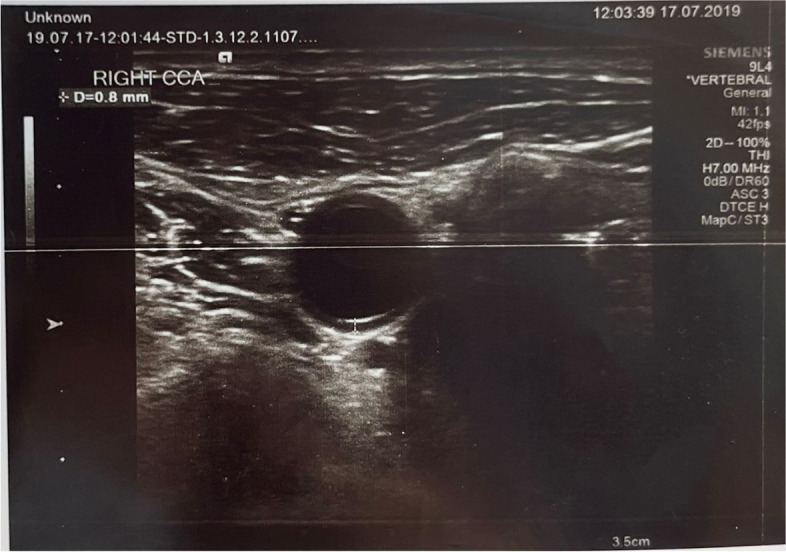

Methods: This study was conducted out between January 2019-December 2019 consisting of a total of 140 participants (70 COPD-diagnosed patients-70 healthy individuals). The COPD-diagnosed patients have been planned according to the selection and diagnosis criteria as per the GOLD 2019 guide. It is planned to evaluate as per prospective matching case-control study of the carotid thickness, radial gas analysis, spirometric and demographic characteristics of COPD diagnosed patients and healthy individuals.

Results: The average Carotid intima-media thickness in COPD patients was 0.8746±0.161 (p<0.05), and the thickness of the carotid bulb was 1.04±0.150 (p<0.05). In the control group, the average CCA intima-media thickness was 0.6650±0.139 (p<0.05), and the thickness of the carotid bulb was 0.8250±0.15(p<0.05) For the carotid thickness that has increased in COPD diagnosed patients a significant relationship is determined between hypoxemia (p<0.05) and hypercapnia(p<0.05). A significant relationship determined between CIMT and severity of COPD (p<0.05) The CIMT was high in COPD patients with hypoxemia and hypercapnia(p<0.05).